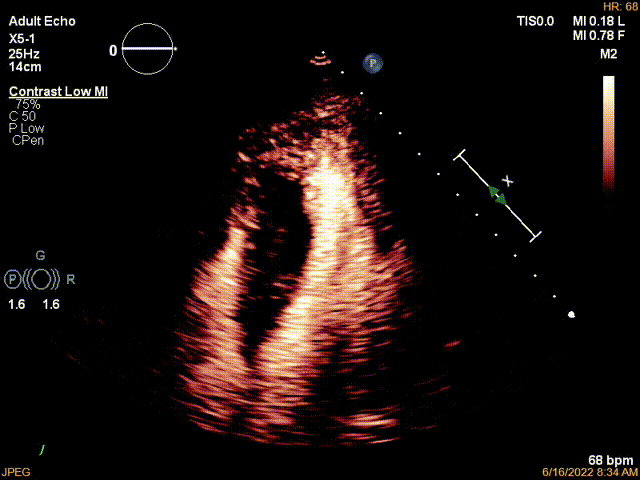

胸骨旁左室长轴切面显示室间隔明显肥厚,左室流出道狭窄